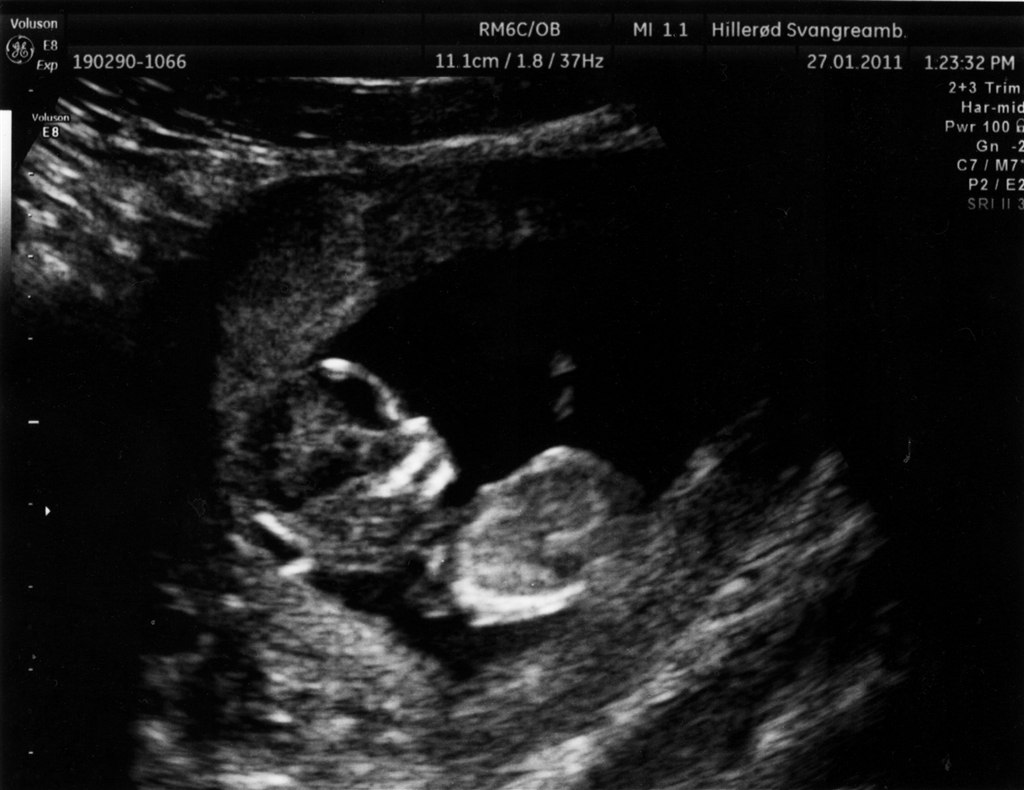

.. Så fik mig og min søde kæreste endelig set det lille liv!

Så fantastisk - intet mindre !

Alt var som det skulle være, og vi har et sundt og rask lille ven, liggende i sin lille hule.

Vedhæftede fotos (klik for at se i fuld størrelse)